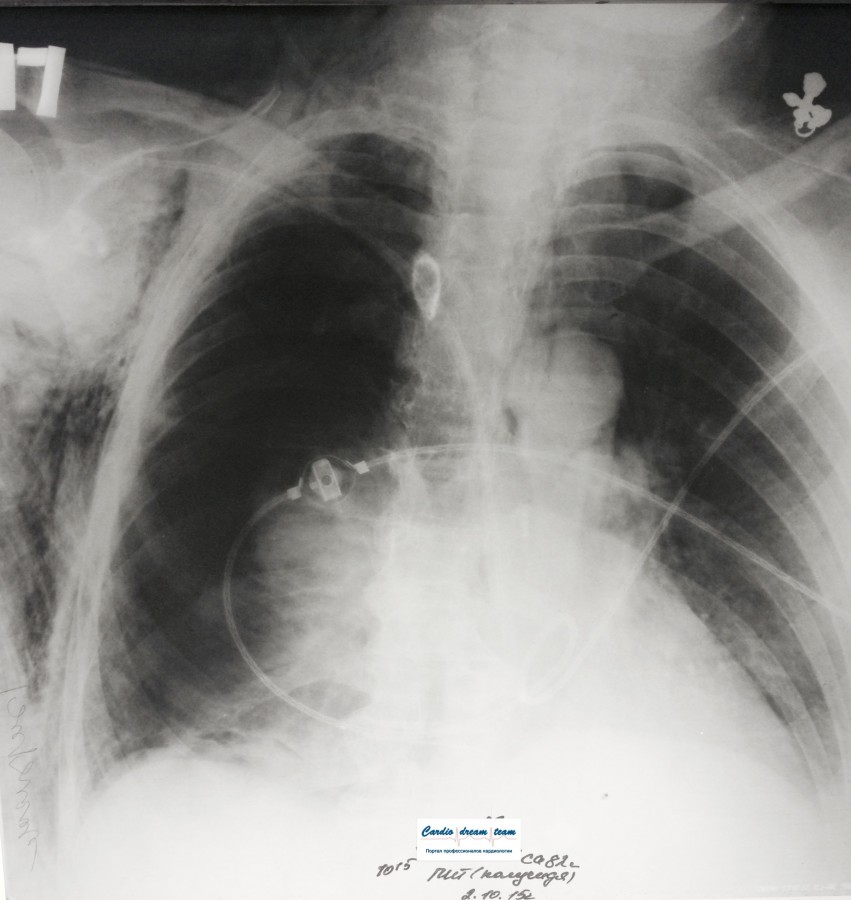

ИССЛЕДОВАНИЕ ОРГАНОВ ГРУДНОЙ КЛЕТКИ Дата 01-ОКТ-15 время 11.30 ОПИСАНИЕ: Проведена рентгенография органов грудной клетки в прямой проекции, положение сидя, условия ПИТ, Р-контроль Легочные поля: Справа легкое расправлено не полностью, апикально до 3го ребра прослеживается свободный газ в плевральной полости. Тень дренажа справа. Тень подключичного катетера в проекции ВПВ. Легочный рисунок: сгущен справа в прикорневой зоне, диффузно деформирован Корни: малоструктурны, обогащены Синусы: нечеткие Сердце: широко лежит на диафрагме (позиционно) ЗАКЛЮЧЕНИЕ: Течение правостороннего пневмоторакса, положительная Р-динамика. Состояние дренирования правой плевральной полости. Р-признаки полнокровия сосудов МКК. Пневмосклероз. Р-контроль .────────────────────────────────────────────────────────────────────── ИССЛЕДОВАНИЕ ОРГАНОВ ГРУДНОЙ КЛЕТКИ Дата 02-ОКТ-15 время 1015 ОПИСАНИЕ:

Проведена рентгенография органов грудной клетки в прямой проекции, положение полусидя, условия ПИТ, Р-контроль Легочные поля: Отрицательная динамика: правое легкое поджато к корню. Тень средостения резко смещена влево. Выраженная подкожная эмфизема мягких тканей грудной клетки справа. Тень подключичного катетера в проекции ВПВ. Легочный рисунок: диффузно деформирован за счет пневмосклероза, сгущен справа Корни: тень средостения смещена влево Синусы: нечеткие Сердце: широко лежит на диафрагме (позиционно) ЗАКЛЮЧЕНИЕ: Правосторонний пневмоторакс, отрицательная Р-динамика. Эмфизема мягких тканей грудной клетки. Пневмосклероз. Р-контроль.